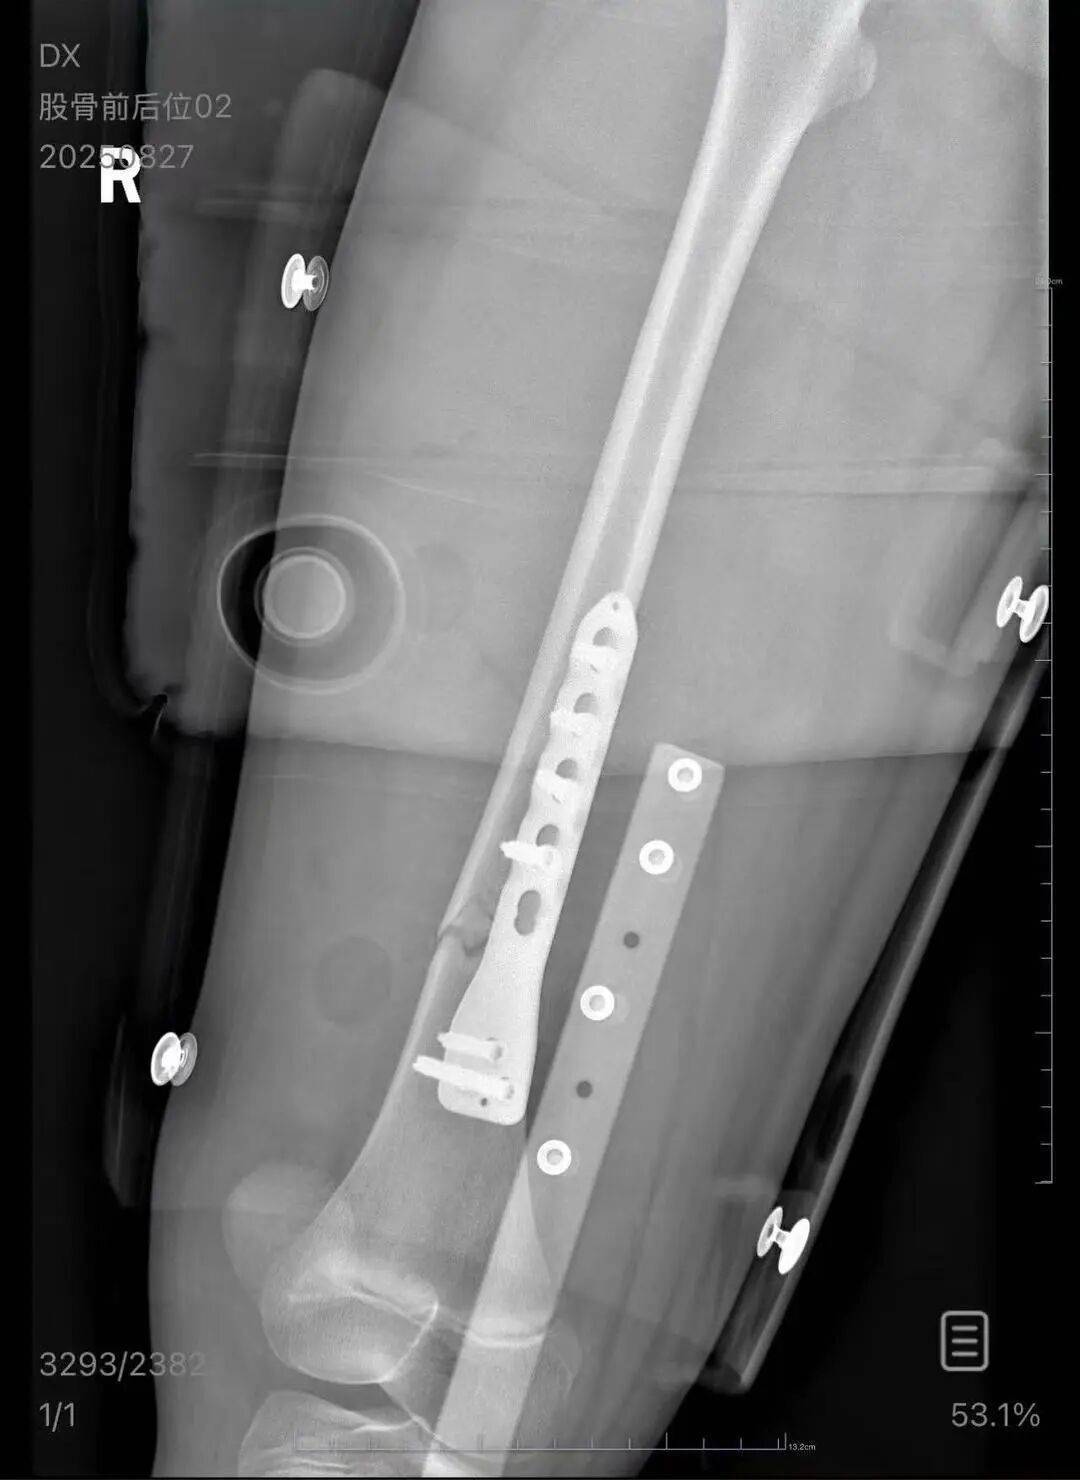

▲朱女士女儿手术后拍的X光片 受访者供图

朱女士向记者出示的医院病历显示,8月24日凌晨,朱女士的女儿到医院就诊。医院诊断朱女士的女儿右股骨骨折,需要住院进一步治疗。